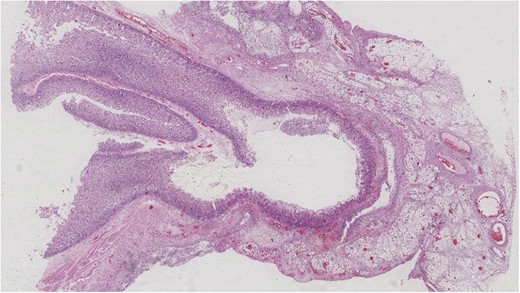

Histopathological examination of the resected specimen confirmed the presence of small bowel diverticular disease. At the site of the exudates, there was prominent serosal inflammation in addition to the inflammation extending from the underlying diverticulum, with obvious intraluminal pus present. These features were in keeping with complicated diverticular disease of the small bowel with secondary perforation (Fig. 3).

Histological examination showing H&E stained jejunal diverticulum.